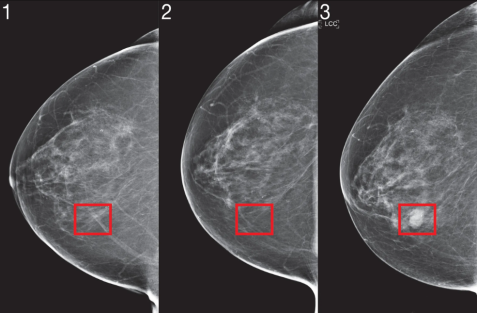

Hình 2: Xquang tuyến vú

Chẩn đoán sơ bộ ban đầu cho ung thư vú bắt đầu bằng khám lâm sàng, chụp

X-quang tuyến vú và siêu âm. Trong một số trường hợp, chụp cộng hưởng từ (MRI) tuyến vú sẽ được thực hiện. Nếu phát hiện khối u, sinh thiết sẽ được tiến hành để đánh giá ung thư trước khi lên kế hoạch điều trị.

Ung thư vú được 'phân giai đoạn' tùy theo kích thước khối u, sự có mặt của các hạch bạch huyết và liệu tế bào ung thư đã lan ra ngoài tuyến vú và các hạch bạch huyết đến các bộ phận khác của cơ thể chưa, theo hệ thống TNM (T – khối u, N – hạch, M – di căn). Thông tin này được sử dụng để giúp quyết định phương pháp điều trị tốt nhất.